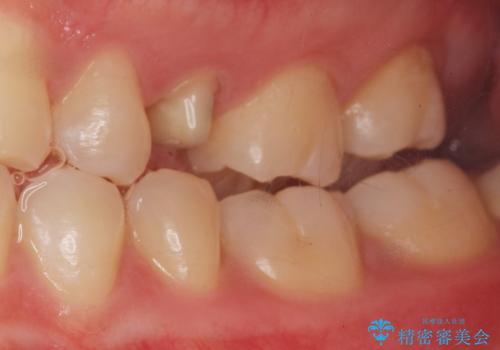

精査したところ、左上の小臼歯(左上5)は被せ物がないまま放置していたことにより、両隣の歯が寄ってきてスペースが少なくなり、また隣の歯(左上4)も虫歯になっていました。

隣の歯の虫歯治療(保険内のレジン充填)後、セラミッククラウンによる補綴を行いました。